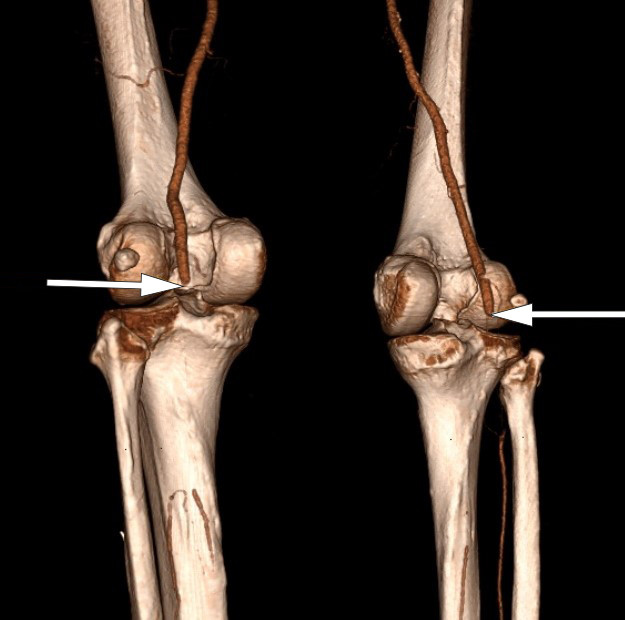

A PCR test on admission was negative for COVID-19 and the patient had no respiratory symptoms. CT angiography showed a filling defect from both popliteal arteries in the knee joint (Figure 1). He also had occlusions distally with localised refilling in the calf arteries, consistent with thrombosis in both lower extremities. The patient was given 5 000 IU dalteparin before being transferred to a regional hospital.

Upon arrival at the regional hospital, the patient had stable respiration and circulation. His lower left extremity was showing signs of acute ischaemia, with pain and reduced sensation, but preserved motor function. The symptoms in his lower right extremity had gradually improved over the course of the day, and the patient now had normal sensation and motor function, but continuing peripheral coldness. An acute bilateral mechanical thromboembolectomy of the popliteal artery and tibiofibular trunk was performed under general anaesthesia. Good circulation was achieved in both lower limbs postoperatively.